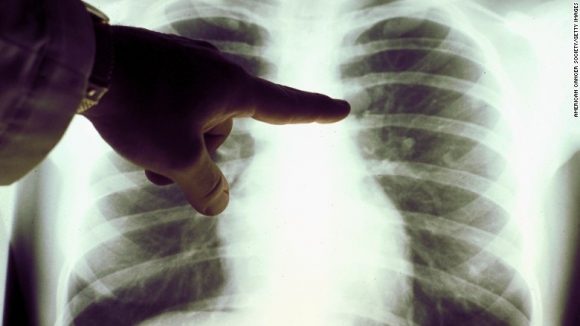

Pero hay una vacuna, concebida y creada aquí en el CIM, que ha llamado la atención de varios países de todo el mundo, incluyendo Estados Unidos. Una vacuna para el cáncer de pulmón.

“El cáncer de pulmón es la tercera causa de muerte por cáncer aquí en Cuba”, dice Rodríguez, sentado en el laboratorio. “Tenemos 4 500 pacientes con cáncer de pulmón cada año. Y en ese mismo período de tiempo, la misma cantidad de pacientes mueren por esta causa”.

Entre los hombres, los tipos más comunes de cáncer son el de pulmón y de próstata. El cáncer de pulmón se ha vuelto particularmente predominante en gran parte gracias a un rubro del país- el tabaco. O más específicamente, los cigarros.

Se llama CIMAVAX, y mientras el CIM la llama vacuna, es importante tener en cuenta que el medicamento no previene la enfermedad como una vacuna tradicional, al menos en su forma actual. En cambio, mantiene los tumores diagnosticados controlados mediante la inhibición de su crecimiento, actuando como un tratamiento. Esto se conoce como una vacuna terapéutica.

En lugar de dirigirse a las células cancerosas directamente, la vacuna actúa como una forma de inmunoterapia, aprovechando el propio sistema inmunológico del cuerpo para combatir el cáncer.

Una serie de ensayos clínicos han permitido que sea probada en 5 000 pacientes en todo el mundo, incluyendo 1 000 en Cuba. En un pequeño ensayo, los pacientes menores de 60 años vivían un promedio de 11 meses más que los que no recibieron la vacuna.